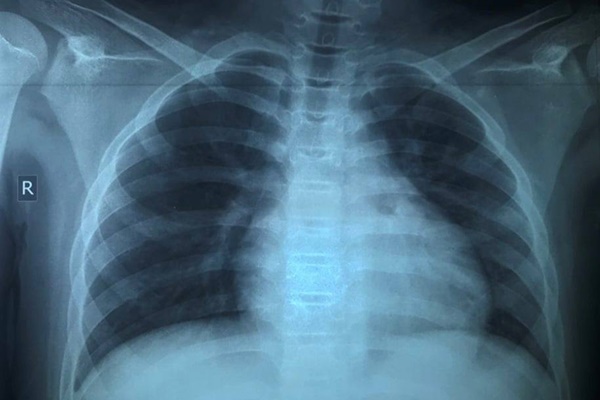

Sau 17 ngày điều trị, tổn thương phổi cải thiện của trẻ được cải thiện. Ảnh: BSCC.

Sau 17 ngày điều trị và theo dõi sát triệu chứng và nồng độ oxy trong máu, bệnh nhi khỏi bệnh hoàn toàn, tổn thương phổi trên X-quang cải thiện đáng kể. Bệnh nhi cũng có kết quả xét nghiệm PCR âm tính. Hiện, trẻ đã được xuất viện.